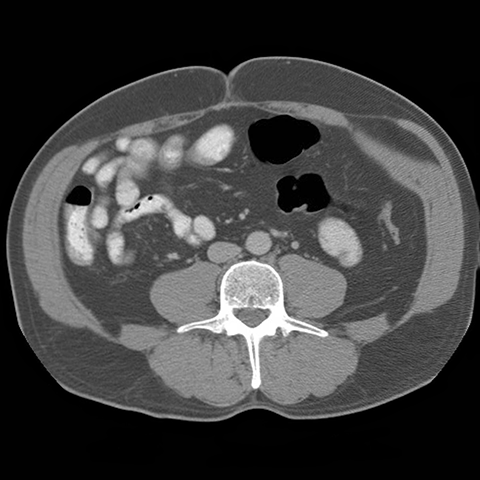

59 year-old male presents with an abdominal mass and pain. [2 of 5]